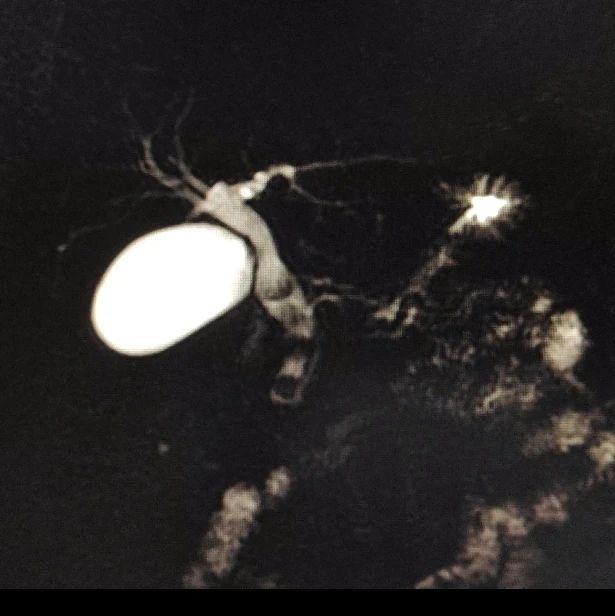

赵女士现年59岁,右中上腹间断性疼痛持续10年。为祛除病痛,于3月3日来吉林省肝胆病医院肝胆外科就诊。主治医师钱峰通过查体发现,患者右上腹压痛明显,结合腹部彩超、CT及MRCP检查,确诊其存在胆总管结石伴胆管炎,并且还患有胆囊结石伴慢性胆囊炎急性发作。

△该图片非案例提及

△该图片非案例提及